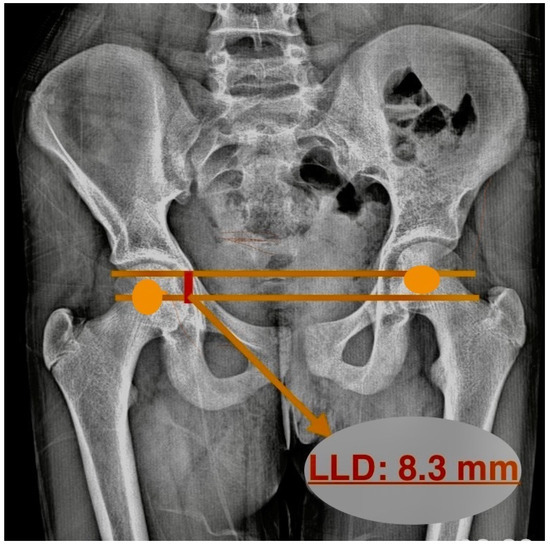

The LLD was determined by drawing two parallel lines between the centers of the femoral heads. Then, the distance between these lines was measured, and LLD was calculated (Figure 3). Pasha et al. determined this value as the inclination of the bifemoral head axis and substituted it for LLD. While this reflects the apparent limb length, it is susceptible to pelvic tilt and may not represent the true anatomical leg length discrepancy [17].

Figure 3. Measuring leg length discrepancy on radiograph.